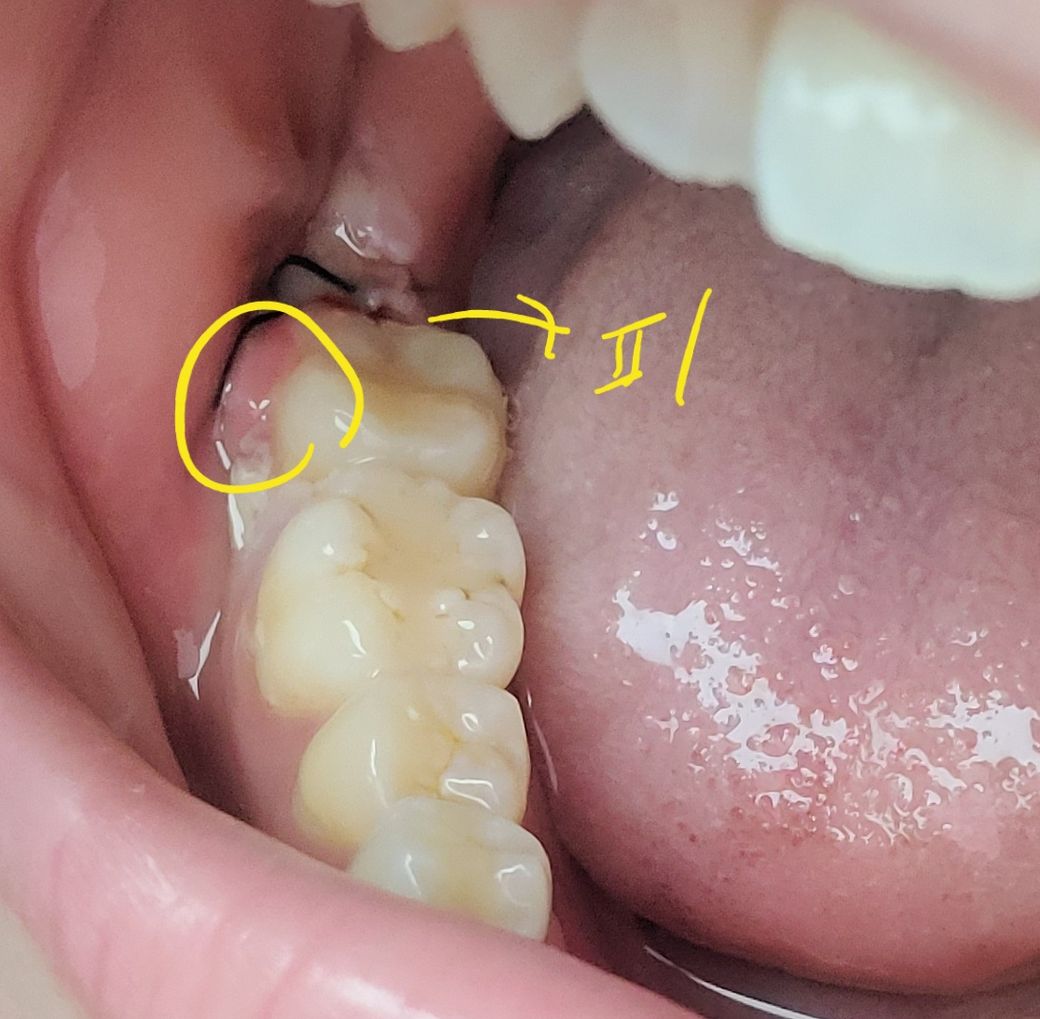

사랑니 발치 옆 어금니 잇몸이 심하게 부었어요

사진처럼 사랑니 발치 바로 옆 어금니 잇몸이 띵띵 새빨갛게 부어서 어금니를 덮었어요 ㅠㅠ 발치 부위 안건드리고 저기만 살짝 건들려도 실밥에서 피가 새어나오더라구요,,

반대쪽 발치 부위는 안그런데 이쪽만 이러네요

실밥 풀면 가라앉는건가요? 아니면 염증이나 고름 생긴걸까요? 발치 5일차입니다

사진 보시고 답변 부탁드립니다ㅠ.ㅠ